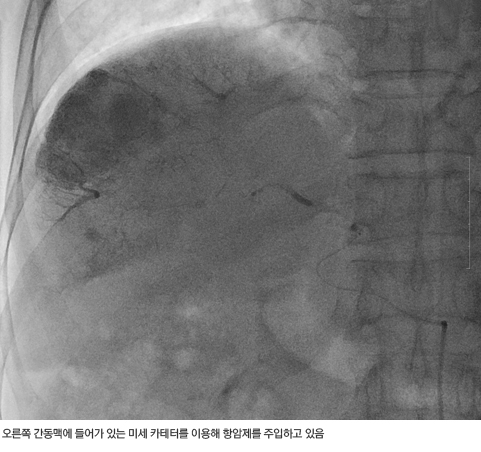

간암 화학색전술로 간암을 치료하는 과정

서혜부(사타구니)에 위치한 대퇴동맥을 통하여 카테터(catheter)라고 하는 약 2~3mm 정도의 가는 관을 삽입하여 간동맥으로 접근한다. 카테터가 간동맥에 들어가면 혈관조영제를 주사하면서 간동맥 조영 사진을 얻어 종양의 위치, 크기 및 혈액 공급 양상 등 치료에 필요한 정보를 얻는다. 치료 방침이 정해지면 종양으로 가는 간동맥을 찾아 항암제와 색전 물질을 (혈관을 막는 물질) 주입한다.